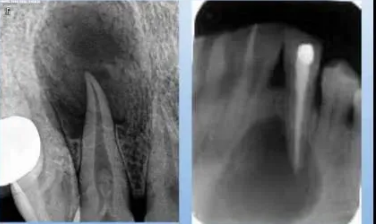

3.根尖囊腫

病理及臨床:囊腫內(nèi)棕黃色液體,常含膽固醇結(jié)晶。早期無(wú)癥狀,囊腫長(zhǎng)大使骨皮質(zhì)變薄,可捫及乒乓感,明顯增大可致骨質(zhì)完全吸收,捫及波動(dòng)感。

X線表現(xiàn):可見病原牙,透射區(qū)邊界清晰銳利,邊緣有致密的骨硬板。